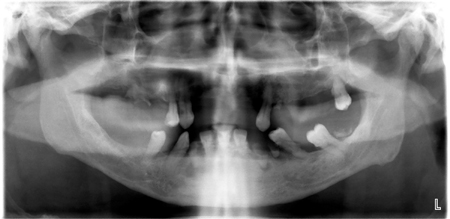

Oral Injury as a Source of Tetanus Inoculation

Davis pan1 alternate text for this image

Abstract Tetanus is a serious, life threatening infection caused by the bacterium, Clostridium tetani. Due to almost widespread vaccination against tetanus toxoid the incidence in the developed world is extremely low. Vaccination in childhood does not result in lifelong immunity and requires “booster” doses of the vaccination every ten years. In the United States, the … Read more